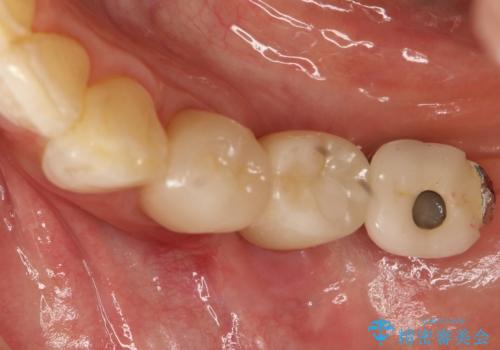

奥歯がない インプラント治療でかみあわせを回復

- 単独のインプラント補綴にて咬合の回復を計画した。

かぶせ物の種類:Bellezza screw retain